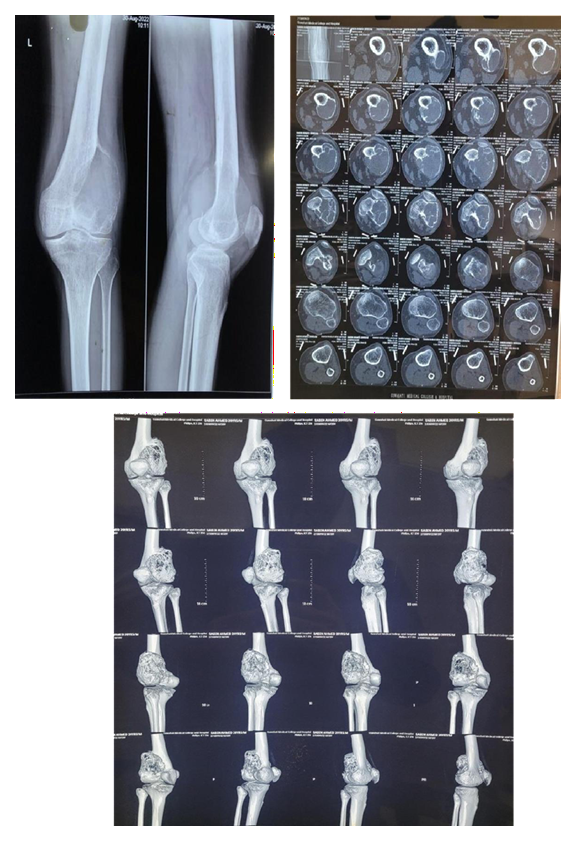

Case 2:

MRI

Pre Denosumab

Post Denosumab

Intraoperative

Post Operative